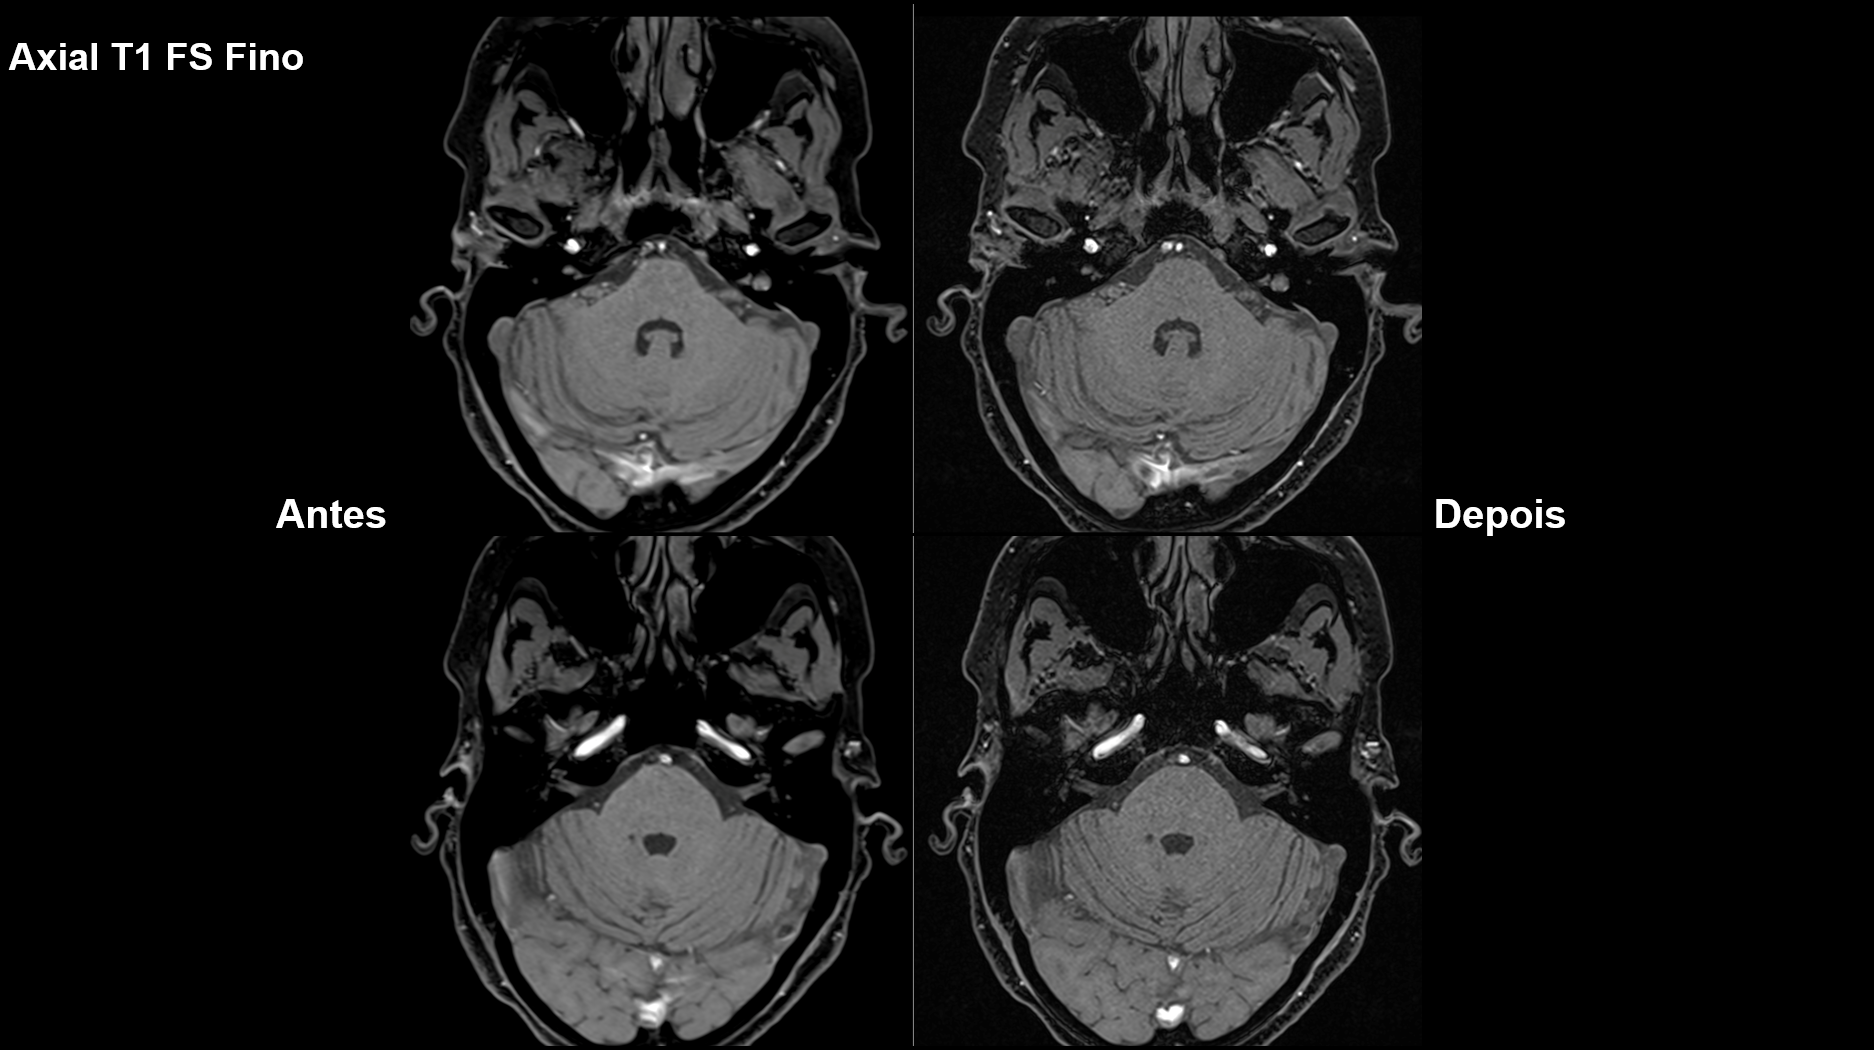

Melhorias implementadas em alguns exames, comparando antes e depois.